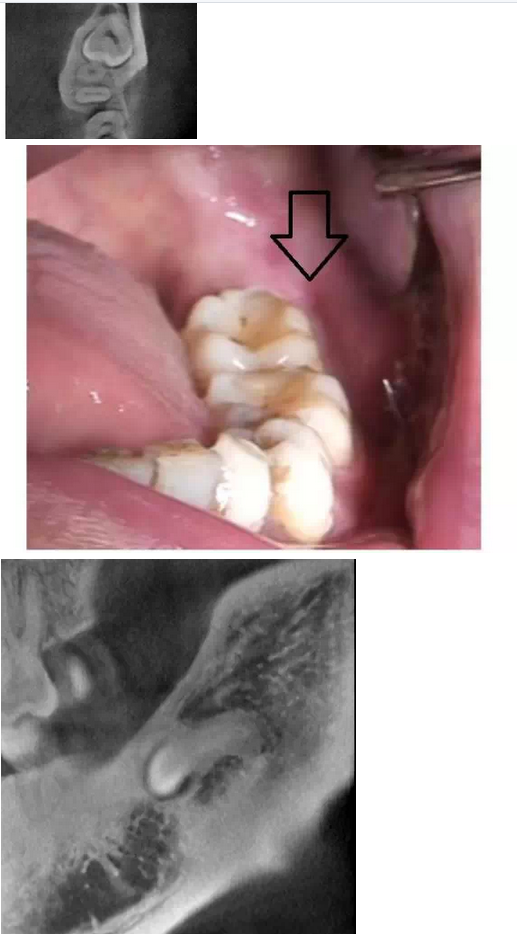

在拔牙一月后,鳥槍換大炮,診所引進(jìn)了三維CT,左側(cè)智齒在拍了CT后,前后頰舌上下關(guān)系就一目了然,此牙更難拔除,因?yàn)橥耆穹▓D二),其上面覆蓋有3mm厚的牙槽骨,其下緣與下牙槽神經(jīng)管緊緊相連,較危險(xiǎn);牙冠前緣與第二磨牙遠(yuǎn)中根也緊緊相連,后緣牙根向上翹;整個牙齒偏頰側(cè),頰側(cè)皮質(zhì)骨板較厚(圖三),舌側(cè)骨板也較厚,測好牙冠頸部上下距離約為9.5mm。

我們掌握了全方位的信息后,藉著CT向患者講解該牙齒的情況,患者充分理解拔牙的風(fēng)險(xiǎn)和醫(yī)生所需要的經(jīng)驗(yàn)和勇氣。因著有CT,術(shù)前的準(zhǔn)備更加充分:手術(shù)切口的設(shè)計(jì)和種植機(jī)去骨的部位選擇均在第二磨牙的遠(yuǎn)中頰側(cè)(圖四);車針長度的定位在9mm,防止磨到神經(jīng)管;掌握了牙根根尖部分是彎向下(圖五),就可以評估常規(guī)的挺子是很難進(jìn)去的,特別設(shè)計(jì)了四把不同角度的挺子。整個拔牙過程非常順利,行云流水,均在我們的掌握之中,猶如四驅(qū)的牧馬,人雖行駛在惡劣的沙漠地,仍是馳騁疆場,酣暢淋漓。

第二顆智齒在CT的輔助下整個拔除時間比第一顆減少了一小時,而且創(chuàng)口小(圖六),術(shù)后反應(yīng)輕,患者在拔除的第二天胸悶的感覺就慢慢消失。